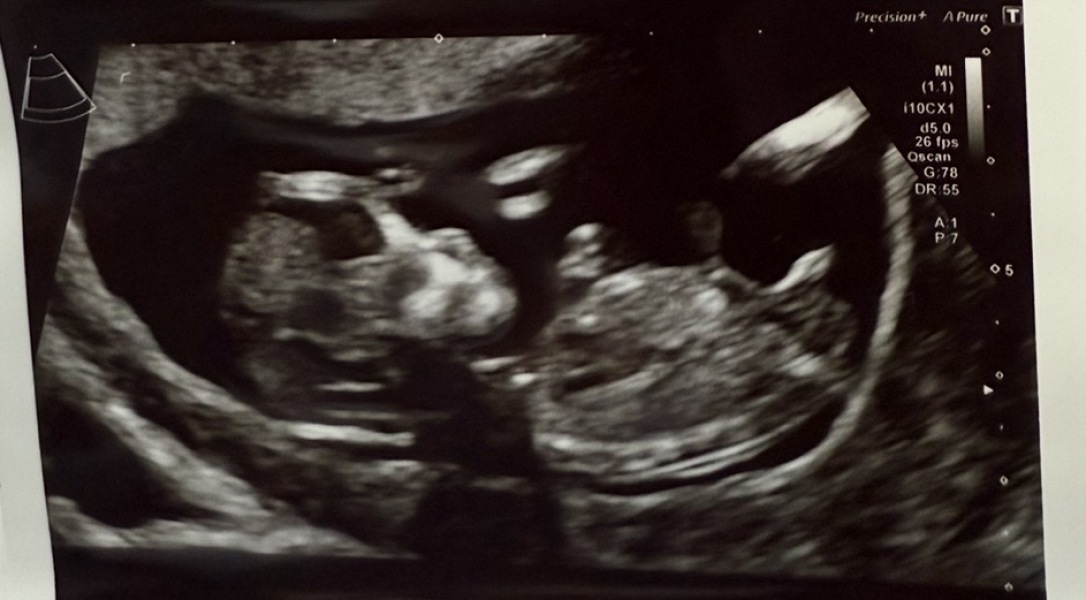

Rainbowbaby25 · 01/06/2025 11:54

Mixed opinions on other forums.

Girl because of bladder position and forked nub, also under 30 degrees and only slightly upward.

Others saying boy because of skull and the nub pointing more up then parrell but not to spine.

12+4 scan